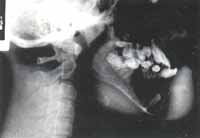

Fig. 10A – Fig. 10B Obsérvese en la radiografía PA (Fig. 10A) gran cavidad quística y la estructura dentada desplazada a la altura del cuello del cóndilo. En la proyección lateral oblicua (Fig. 10B)

se aprecia el desplazamiento del tercer molar y el aspecto multilocular de la lesión. Esta secuencia

corresponde a la fase diagnóstica del caso.Fig. 10 A